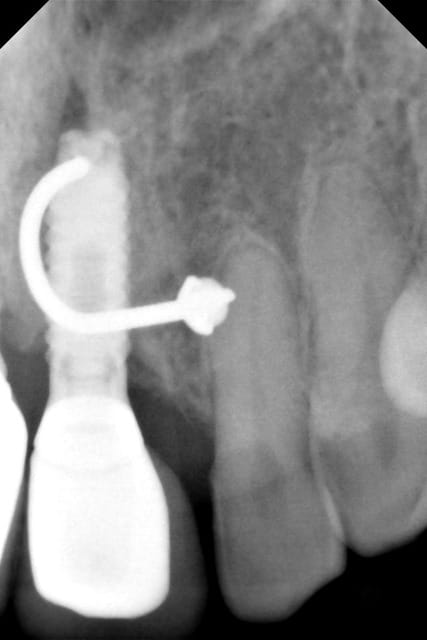

salut à tous: j'ai reçu ce matin une patiente pour un pilier d'implant qui semble se dévisser.

Malheureusement je n'y connais pas grand chose je suis orienté endodontie. Mais j'aimerai la dépanner en l'adressant à quelqu'un capable de la prendre en charge.

C est une patiente qui s 'est fait poser les implants il y a 15 ans dans une autre région par un praticien qui serait parti à la retraite donc peu de piste pour trouver le type d'implants.

J'ai 2 radios rétro est ce que quelqu'un peut m'aider?